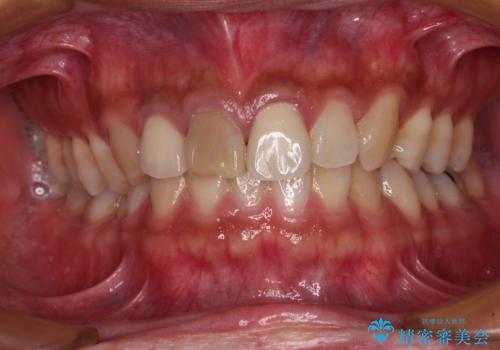

- 前歯の変色した歯を治したいことを主訴として来院された患者様です。

数年前、外傷により両隣の歯とともに根管治療を行い、その後両隣の歯はオールセラミッククラウンにて補綴したそうです。

時間の経過とともに、セラミックにしなかった当該歯の変色が目立つようになり、オールセラミッククラウンにて補綴することとしました。